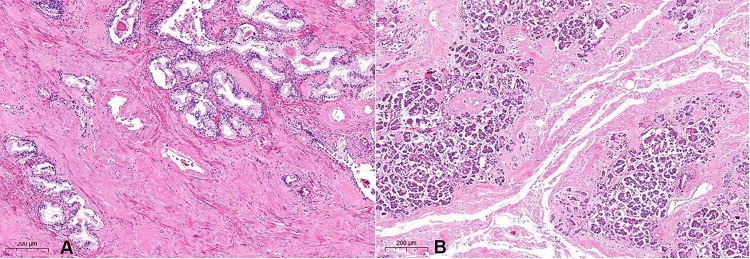

Regarding the alimentary tract, a diffuse dilatation of the stomach and bowels with scattered dark-green colored intestinal segments, emphysematous enteritis (pneumatosis intestinalis), and diffuse loss of the mucosal folds were observed (Figure 7A and 7B). Histologically, there was coagulative ischemic necrosis of the mucosa (Figure 7C). A large amount of amyloid protein deposits was found in the mesenteric and intestinal blood vessel walls (Figure 7D), which may have hampered the bowels’ perfusion and caused the ischemic findings.